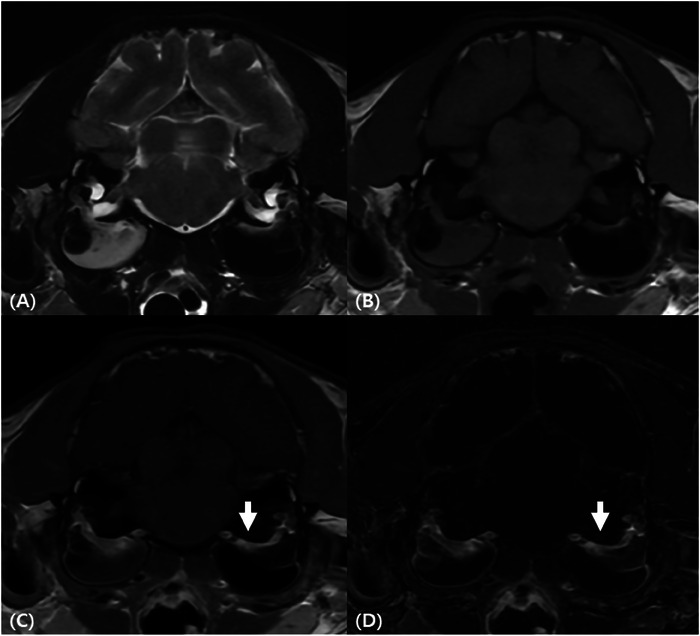

Evaluating the morphological changes of the tympanic bulla and the contrast enhancement (CE) patterns are key factors in diagnosing otitis media and predicting its underlying etiology. However, limited research exists on the CE patterns of the tympanic bulla in cats with bulla effusion. This retrospective study aimed to investigate the prevalence and patterns of CE in the tympanic bulla based on the presence and severity of bulla effusion in cats. Feline head CT or brain MRI images from six institutions were analyzed. Transverse pre- and postcontrast CT and MRI images were reviewed to assess the presence and severity of bulla effusion, along with the presence, pattern, and location of tympanic bulla CE. A total of 644 tympanic bullae from 322 cats were included. Bulla effusion was detected in 105 of 644 bullae, while CE was observed in 73 of 644 bullae: 5 of 539 bullae without effusion and 68 of 105 bullae with effusion. CE was significantly more common in cats with bulla effusion, with the incidence increasing as effusion severity progressed. Focal rim enhancement, predominantly localized to the dorsal aspect of the tympanic bulla, was the most frequent enhancement pattern. In cases with mild or moderate bulla effusion, only focal dorsal enhancement was observed. However, in cats with severe bulla effusion, additional patterns, including focal ventral or lateral, complete rim, and internal enhancement, emerged. These findings suggest that both the incidence and patterns of CE evolve with the progression of bulla effusion in cats and that focal dorsal enhancement may be an early indicator.